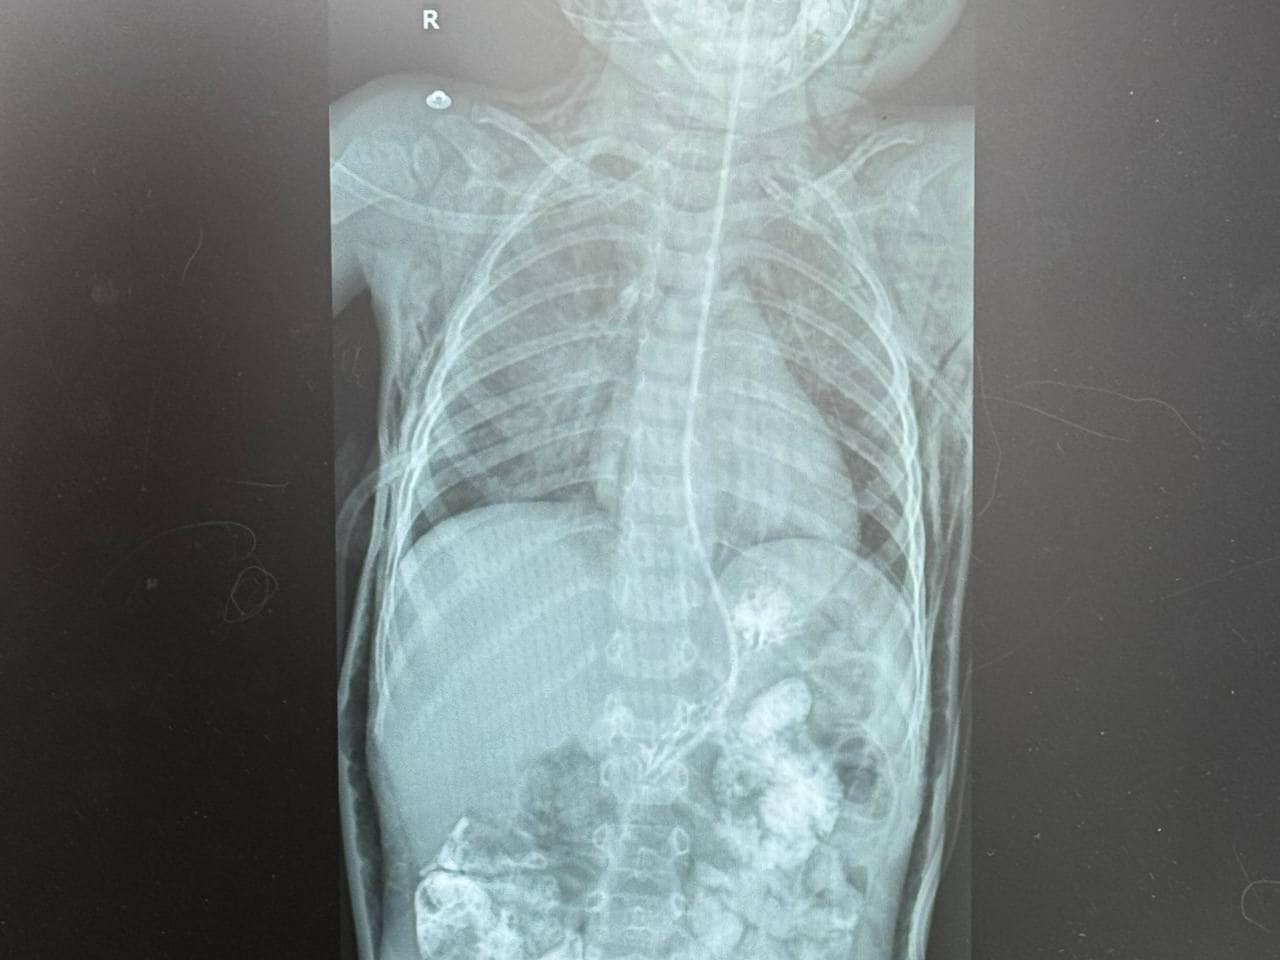

У рідному місті, де Луку під час стоматологічного лікування інтубували, мама хлопчика помітила, що у сина почало боліти горло, з'явилися набряки на шиї, голові та обличчі, а дихання стало утрудненим. Термінове звернення до місцевої лікарні виявило накопичення повітря в середостінні, під шкірою голови, шиї та грудної клітки, що свідчило про порушення цілісності дихальних шляхів.

Луку терміново доставили до «Охматдиту», де спеціалісти виявили розрив трахеї довжиною 2,5-3 см. Того ж дня була проведена операція, під час якої медики успішно зашили і відновили цілісність трахеї.